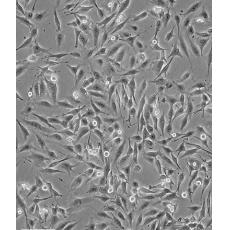

中文名稱 人乳腺癌高轉(zhuǎn)移細胞

組織來源 乳腺癌

細胞種屬 Homo sapiens, human

生長特性 loosely adherent with floating clusters

形態(tài)特征 epithelial

細胞描述 該細胞1976年建系,源自一位48歲患有乳腺癌女性的胸腔積液,但近來有研究證明該細胞被M14黑色素瘤細胞污染。